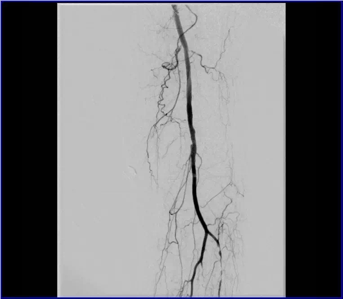

動(dòng)脈閉塞處支架植入